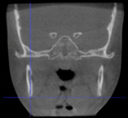

Three points determined the Acta plane: O, F right (FR), and F left (FL) (Table 2). Point O is the midpoint between the most craniodorsal point of the dorsum Sella and the most posterior dorsal point of the Basion in the midsagittal plane (Figure 1). Both points F are a result of the intersection between two lines: the line that connects the most inferior points of the lower orbital margins, right and left, and a line perpendicular to this line that runs through the most external points of the orbital margins, right and left (Figure 2). The new transverse reference plane, the Acta plane (Figure 2), is created by connecting the O-point (Figure 1) with FR and FL (Figure 2).

Figure 2.

(A) Construction of the F-points (right and left), frontal view. The F-points are originated from the intersection between the line connecting points A (the most inferior point of the lower orbit) and the perpendicular line to it that passes through points B (most external/lateral point of the Orbita). (B) Transverse view of the ACTA plane.